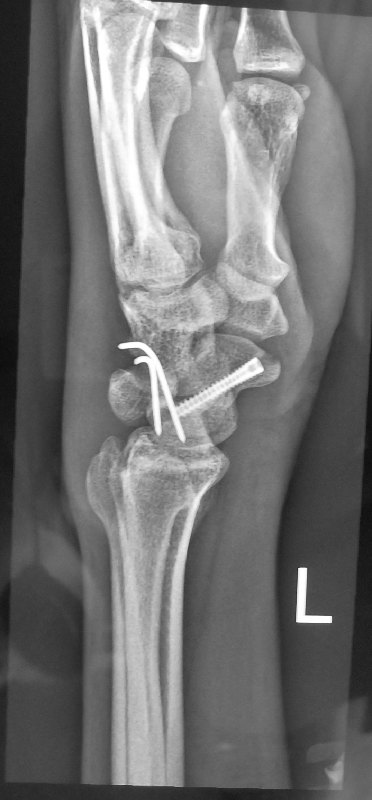

This is how the x-rays looked like after the surgery:

For definitive treatment of this injury, the patient required an open reduction and fixation of the scaphoid fracture together with reduction and stabilisation of the luno-triquetral joint to allow the lunotriquetral ligament to heal.